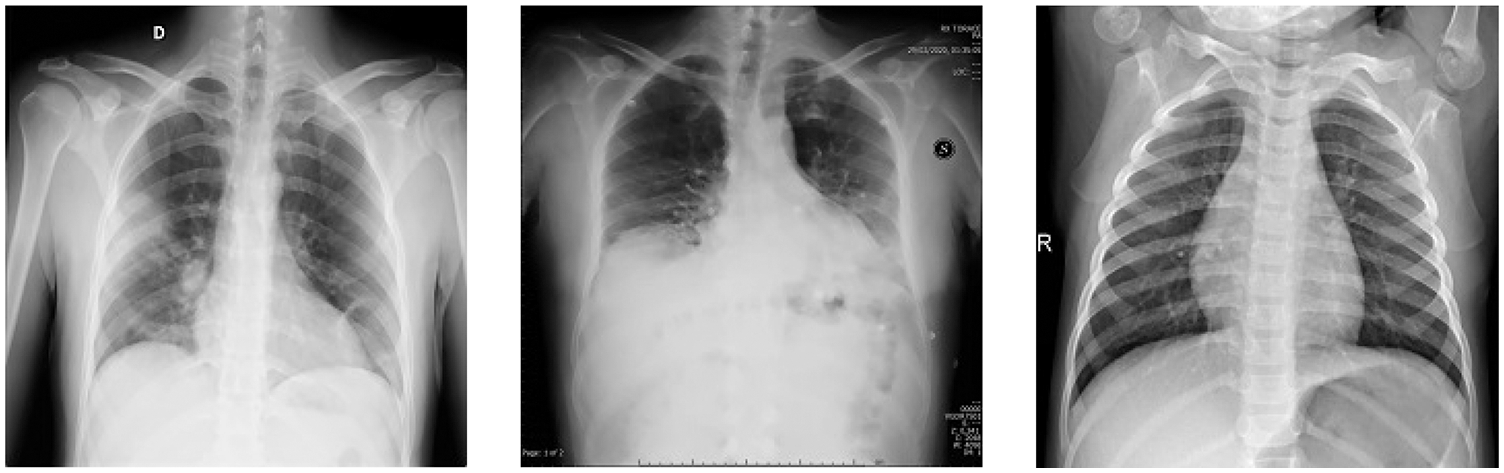

Finally, to enhance the image quality by reducing noise from raw images, Crimmins speckle removing filter is applied. The Crimmins speckle removal filter reduces the speckle noise by analyzing each pixel of the image in a sliding window fashion. It minimizes salt and pepper noises by following the steps described in Section 2 of this paper. Few filtered images are shown in Fig. 8.

Figure 8: Filtered image samples using Crimmins speckle removal filter